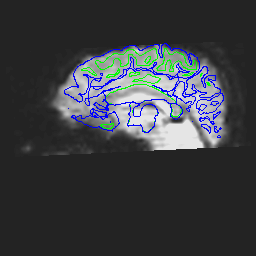

A qualitative way of judging the effectiveness is to overlay the unwarped EPI on the T1 and see how they match.

Here are corrected EPI images with the gray and white matter boundaries overlaid.